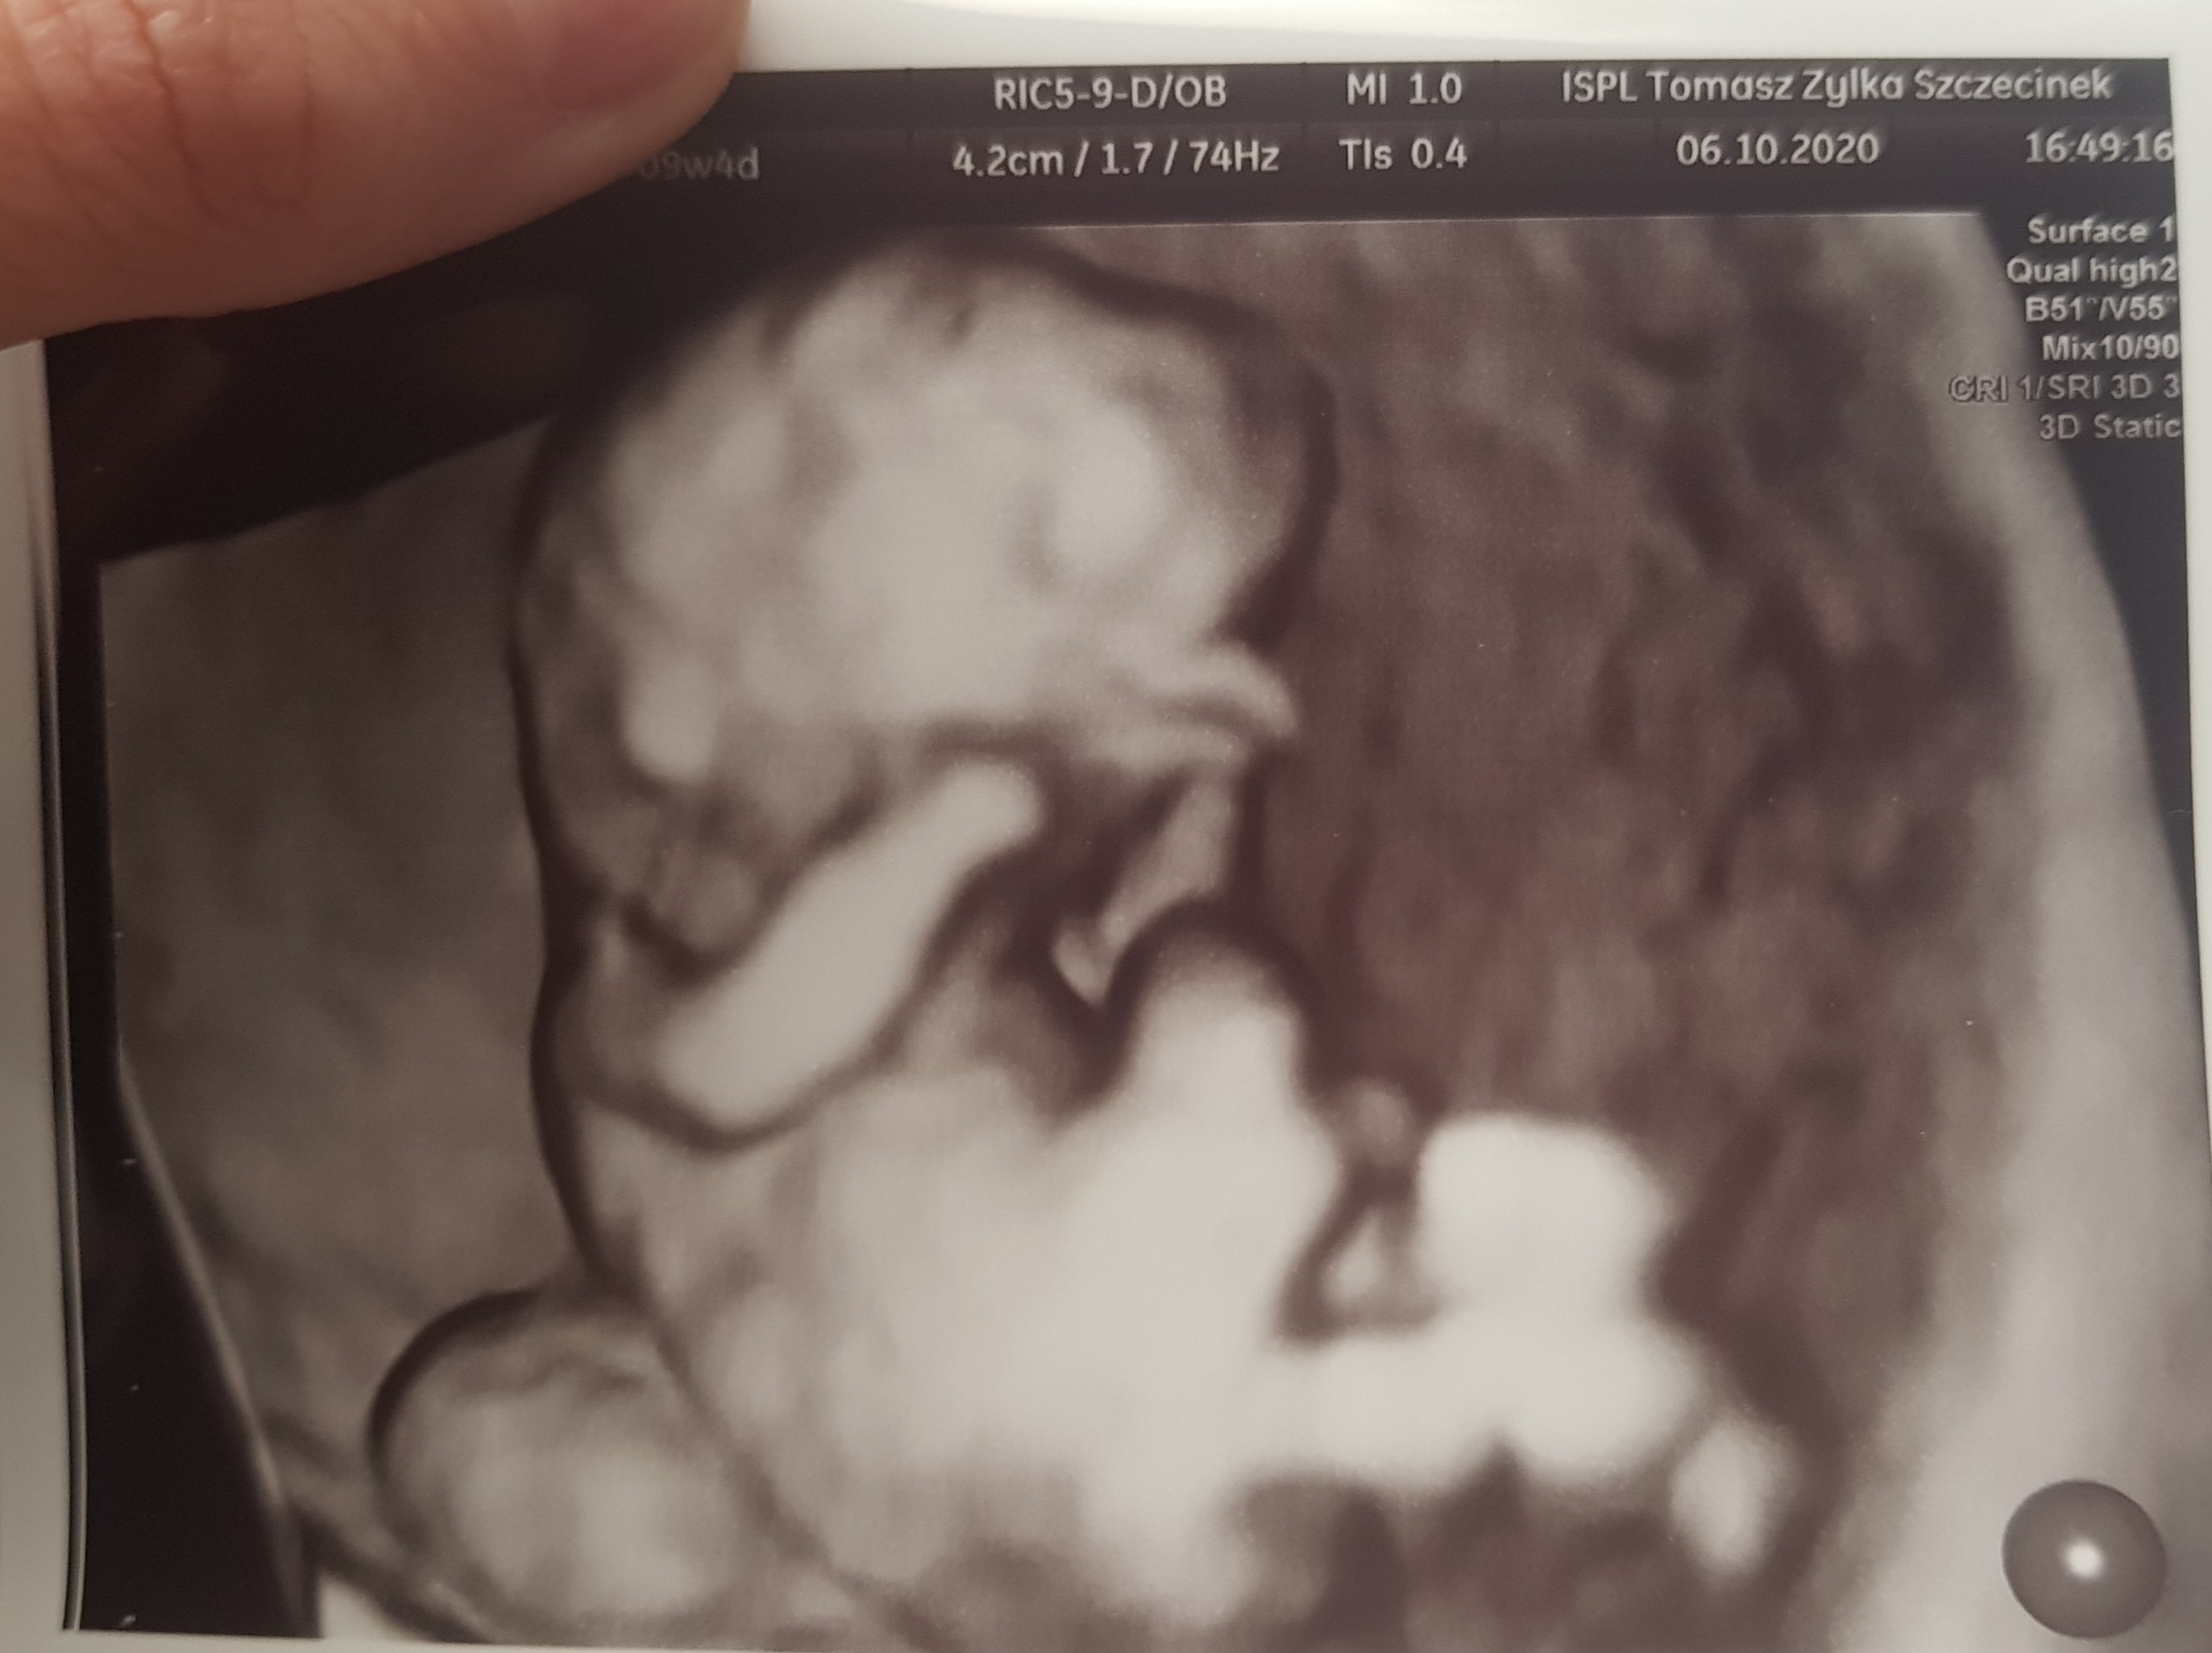

Tak stresu co nie miara. Czekałam na jakieś zle wiadomości przez to że się człowiek naczyta. Jestem na l4 od dziś i mam zamiar już nie myśleć źle tylko cieszyc sie z dzidzi. Wczoraj dopiero uwierzyłam.

Załączniki

• 20201007_061500.jpg

ale śliczne zdjęcie